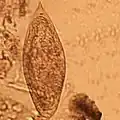

In de slak ondergaan de larven een aantal ontwikkelingsstadia. De miracidia verliezen hun trilharen en veranderen in een moeder-sporocyst: een soort zak waarin de larve zich ongeslachtelijk vermeerdert. Iedere moeder-sporocyst produceert meerdere dochter-sporocysten, die op hun beurt weer talloze cercaria (larven) voortbrengen. Ieder miracidium brengt zo vele honderdduizenden cercaria voort. Ook van de cercaria zijn er mannelijke en vrouwelijke exemplaren.

De cercaria verlaten hun tussengastheer en zwemmen naar hun tweede gastheer. Mensen kunnen besmet raken door te baden, waden, zwemmen, drinken en wassen. De larven dringen de (gave) huid binnen en ontwikkelen zich daar tot een schistosomulum, een nieuw larvestadium. De schistosomula komen in het bloedvatenstelsel terecht, waarin ze uitgroeien tot volwassen mannelijke en vrouwelijke wormen. De exacte leefwijze verschilt per soort.